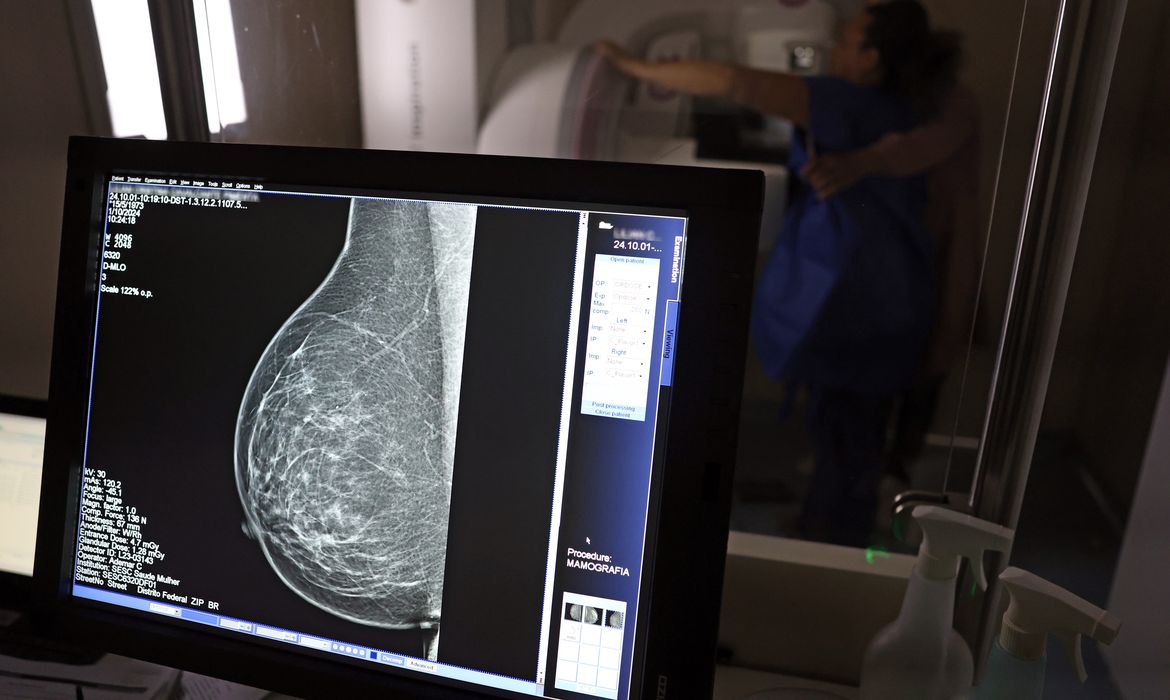

No Outubro Rosa, o Instituto Nacional de Câncer (Inca) estimou 73.610 novos casos este ano no país. É o câncer que mais mata mulheres no Brasil. As mulheres em tratamento pela doença têm o direito de receber o auxílio-doença ou o benefício de prestação continuada.

A vice-presidente da Comissão de Previdência Social Pública da Ordem dos Advogados do Brasil do Rio de Janeiro (OAB-RJ), Danielle Guimarães, destaca que o câncer de mama é uma das doenças que mais afetam mulheres no Brasil, impactando não apenas a saúde física e emocional, mas também a capacidade de trabalho e a segurança financeira das pacientes.